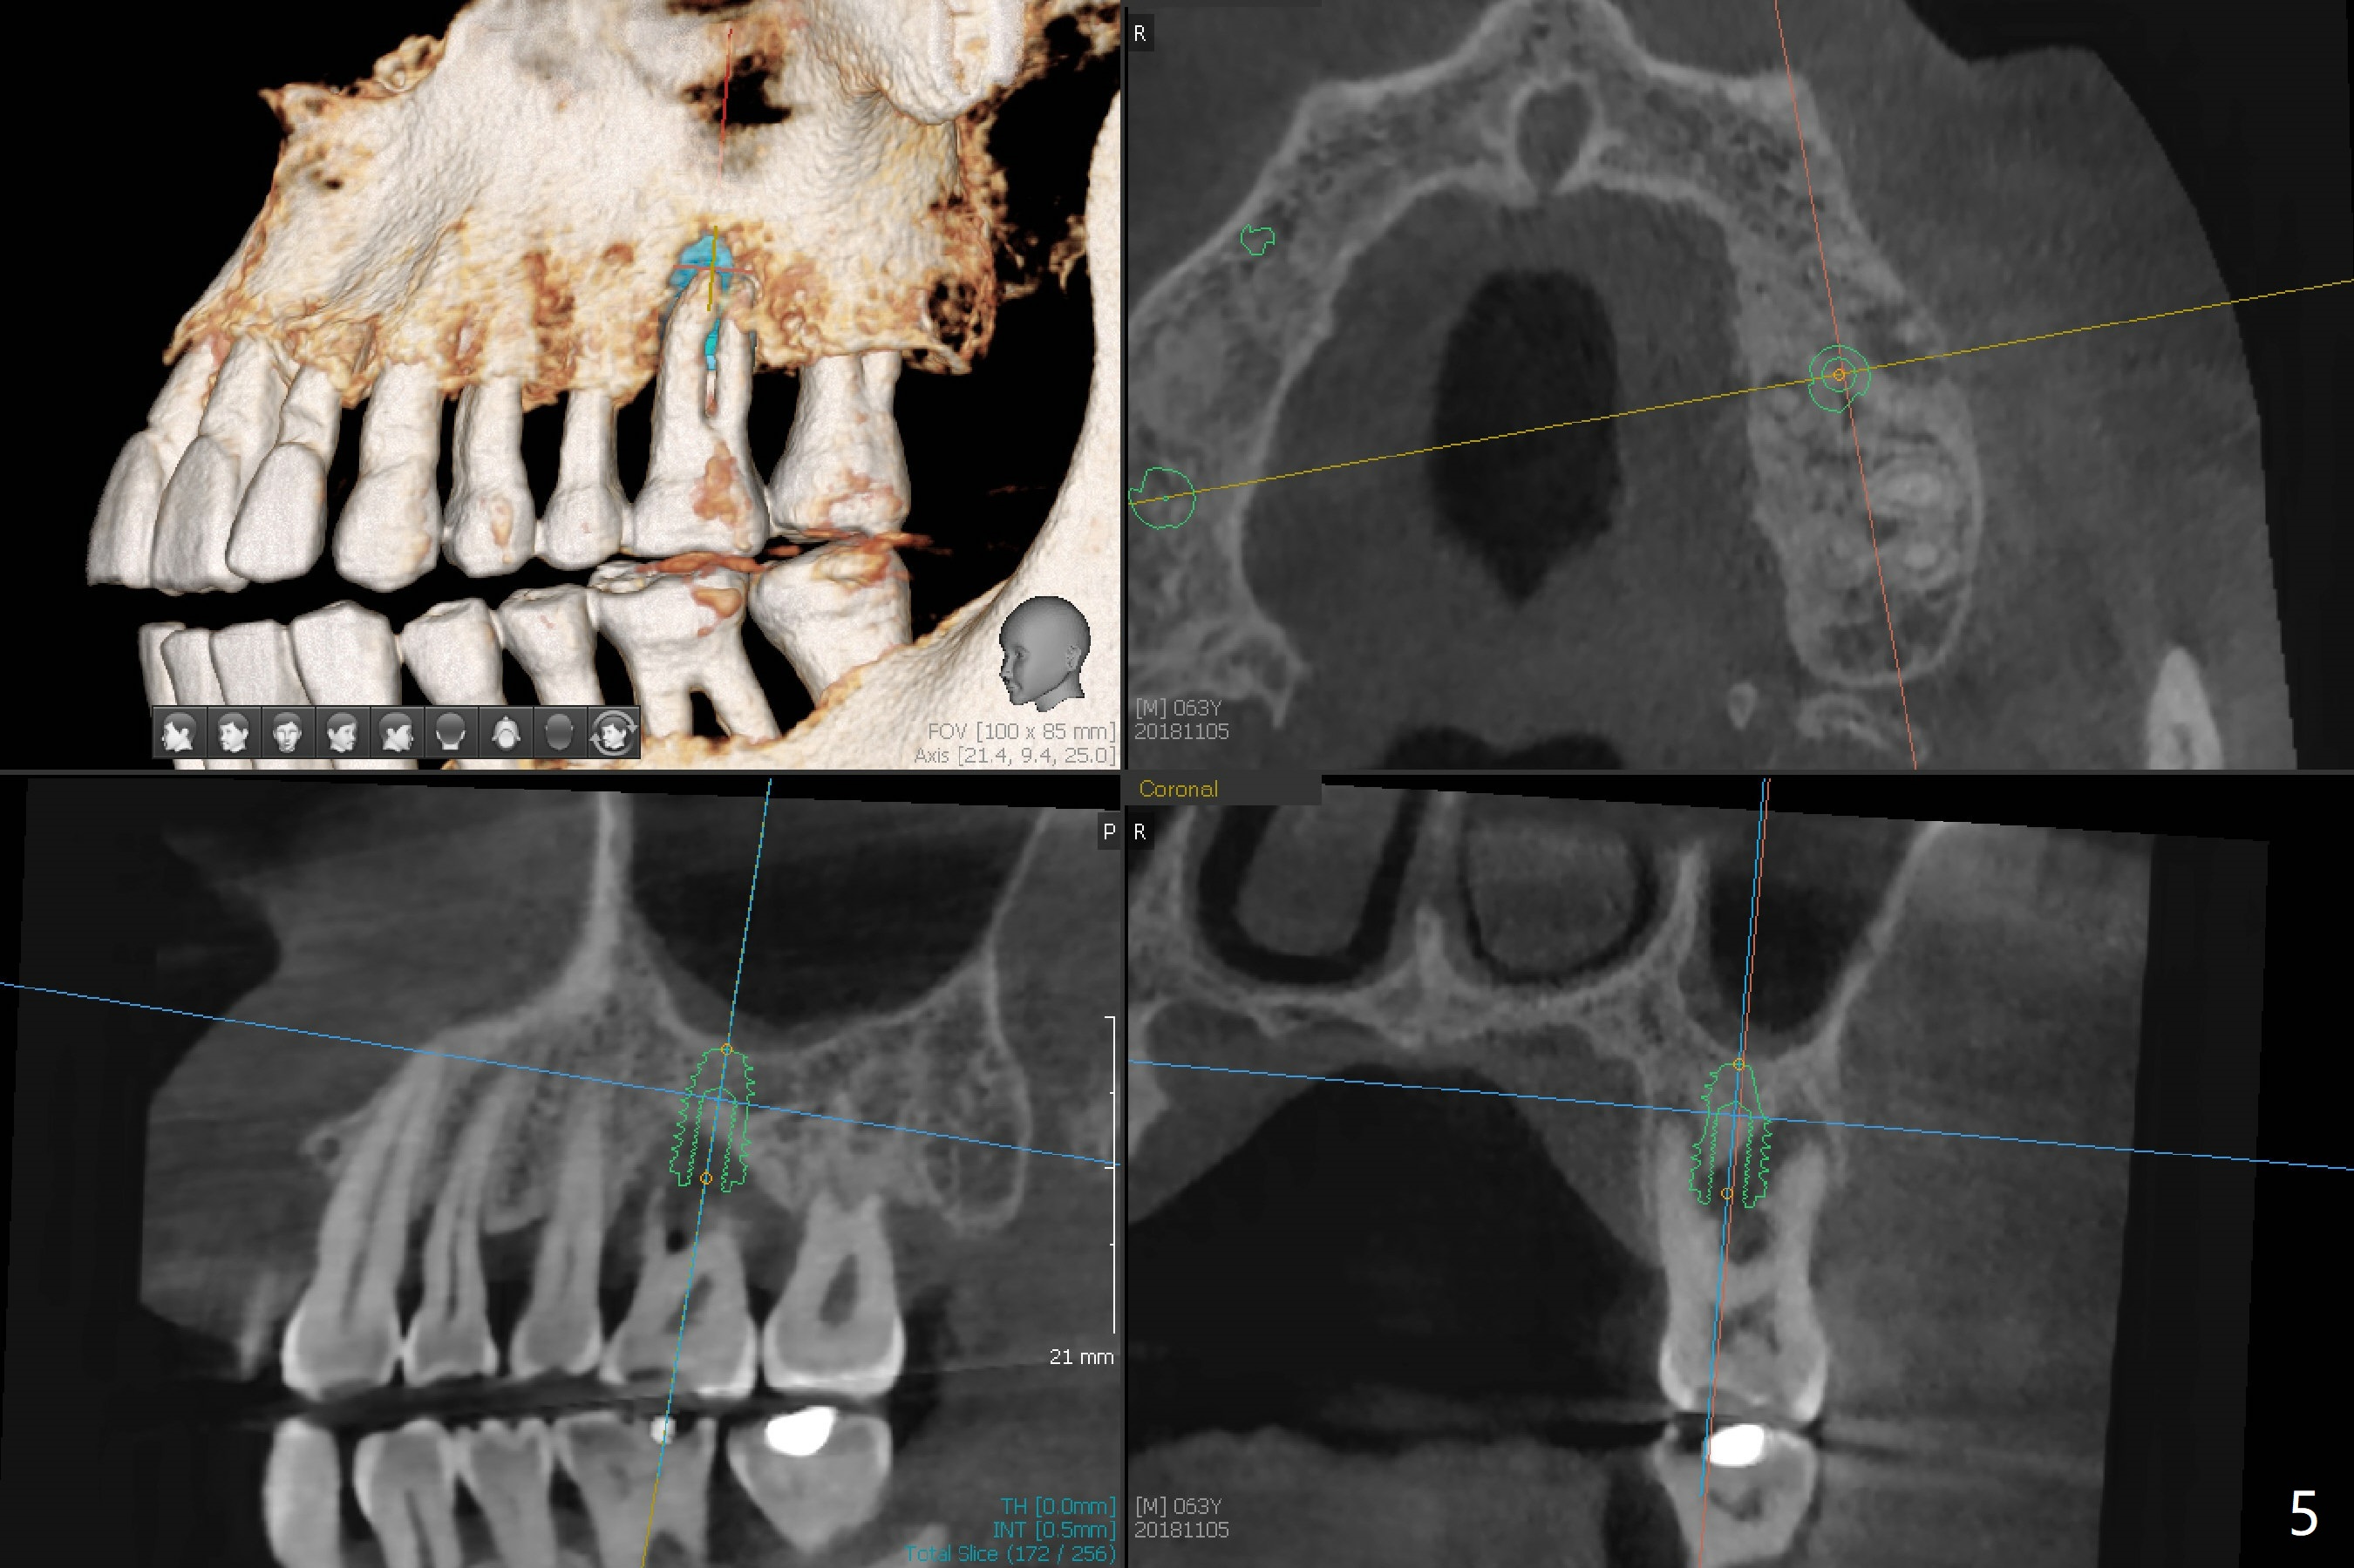

A 63-year-old man lives out of state and returns to office for scaling with chief complaint of occasional upper left pain (#14, Fig.1). After discussion, he agrees to have implant restoration in the upper right quadrant (#2-4). It appears that a 3-unit FPD is appropriate (Fig.2,3). When the teeth #14 and 19 fail, immediate implants will be placed (Fig.4-6).